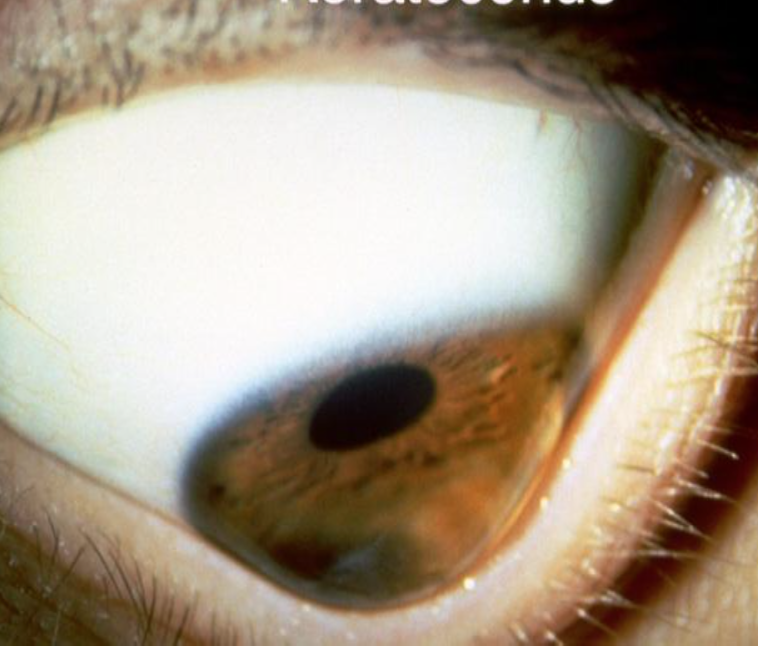

Hva er dette?

Keratokonus